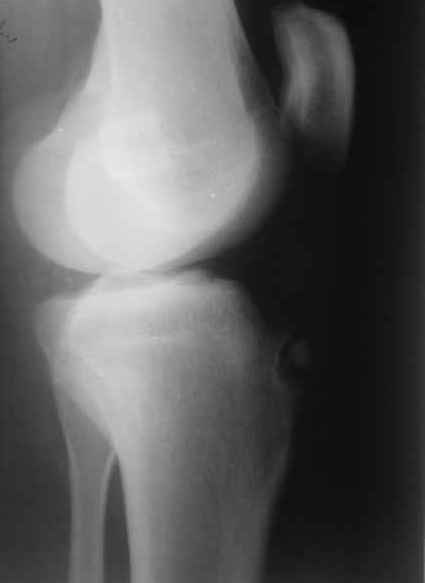

Здравствуйте, коллеги.Вопрос (как и предыдущий) опять из разряда "кислых" :)))Мужчина 30 лет. Жалобы на резкий отек и боли в коленном суставе.

Травму и значительные физические нагрузки исключает. На рентгене - некроз бугристости большого берца. На фоне иммобилизации конечности задней гипсовой шиной и назначения НПВС отек и боли чудесным образом купированы :)))) В анамнезе болезнь Озгуда-Шлаттера, благополучно отслужил в вооруженных силах. До сегодняшнего момента ничего не беспокоило. На снимке вижу отрыв некротически измененного участка бугристости берца. Разгибание в коленном суставе восстановлены. Встал вопрос о дальнейшей тактике лечения такого пациента. Отправить пациента к краевым кудесникам, либо можно обойтись своими силами? Операция? Консервативное лечение?-- С уважением, Заднепровский Никита Николаевич

Это диссекат, не отрыв.

Если все купировалось - пусть гуляет. Если обострений не будет, или редко - тот же подход. Если более часто, пациенту это сильно докучать будет - иссечь этот фрагмент.

Удалить фрагмент и больше ничего не надо.

А в данном случае индекс Блэкберн и Пилл 0.75.

Есть подозрение на пателла альта.